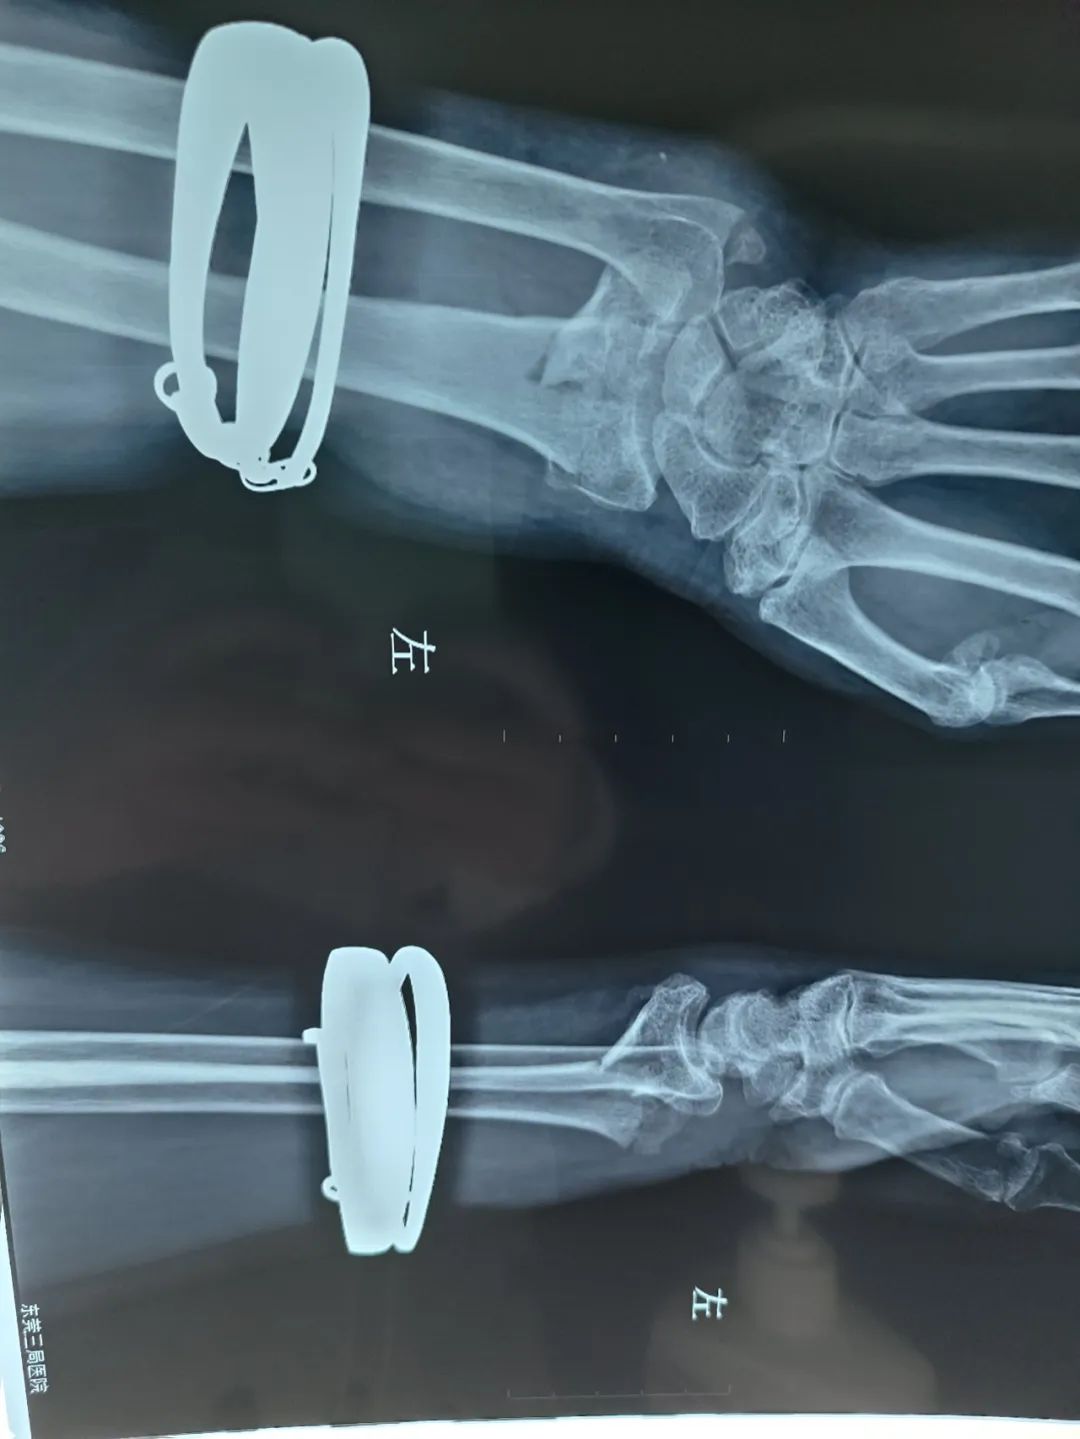

左手摔断,中医正骨快速复位,免除手术痛苦!

左桡骨远端粉碎性骨折伴尺骨茎突骨折

主治医生:尹志良 晚上9点一阵手机铃声响起,“尹主任您好,家里老人家摔伤手怎么处理?”尹主任告诉他:先拍片看是否有骨折。半小时后患者家属再次来电说:“左手摔断了,医院建议手术治疗",但家属想老人家年龄大,希望看看能不能不用手术,做中医保守治疗。 罗奶奶,80岁,左手摔伤一小时,左手活动受限。拍片示:左桡骨远端粉碎性骨折伴尺骨茎突骨折。 体查:痛苦面容,左手肿胀明显,活动受限,关节畸形。 诊断:左桡骨远端粉碎性骨折伴尺骨茎突骨折 治疗:根据患者病情采用中医正骨手法复位及小夹板固定,中药外敷。 当晚拍片示:骨折处对位结线明显好转,患者感疼痛明显改善。 之后患者经过的中药外敷换药与针灸治疗,加上手法康复治疗, 一个月后基本恢复正常,可以正常活动。 温馨提示 1、摔伤后第一时间如果有出血先止血,如果没有出血情况马上进行冰敷。 2、如果疼痛、肿胀明显建议医院拍片。 3、48小时内禁止擦药油及使用任何活血化瘀药物。 4、如果有骨折建议找专科医生诊治。 扶正堂医疗团队简介 东莞清溪/南城扶正堂中医医疗团队在刘永坚主任带领下,十九年专注于运动损伤,中医骨伤、手术后康复,脊柱相关疾病,体能康复,中医内科、中医儿科、中医妇科、中医眼科等疾病的治疗预防与研究;全部采用中医传统疗法,结合功能康复解决各类疑难杂症的困扰,安全无害,快捷有效,对人体无任何伤害。 咨询电话 13790481751 尹志良医生 (清溪) 13414361801 蒋文波医生 (南城) 联系方式 社保定点医疗机构 东莞清溪扶正堂中医门诊部 地址:东莞市清溪镇埔星西路8号 电话:0769-87322222 微信:18027573801 东莞南城扶正堂中医门诊部 地址:东莞南城区簪花路达鑫龙庭108号 电话:0769-88009168 微信:18122872217